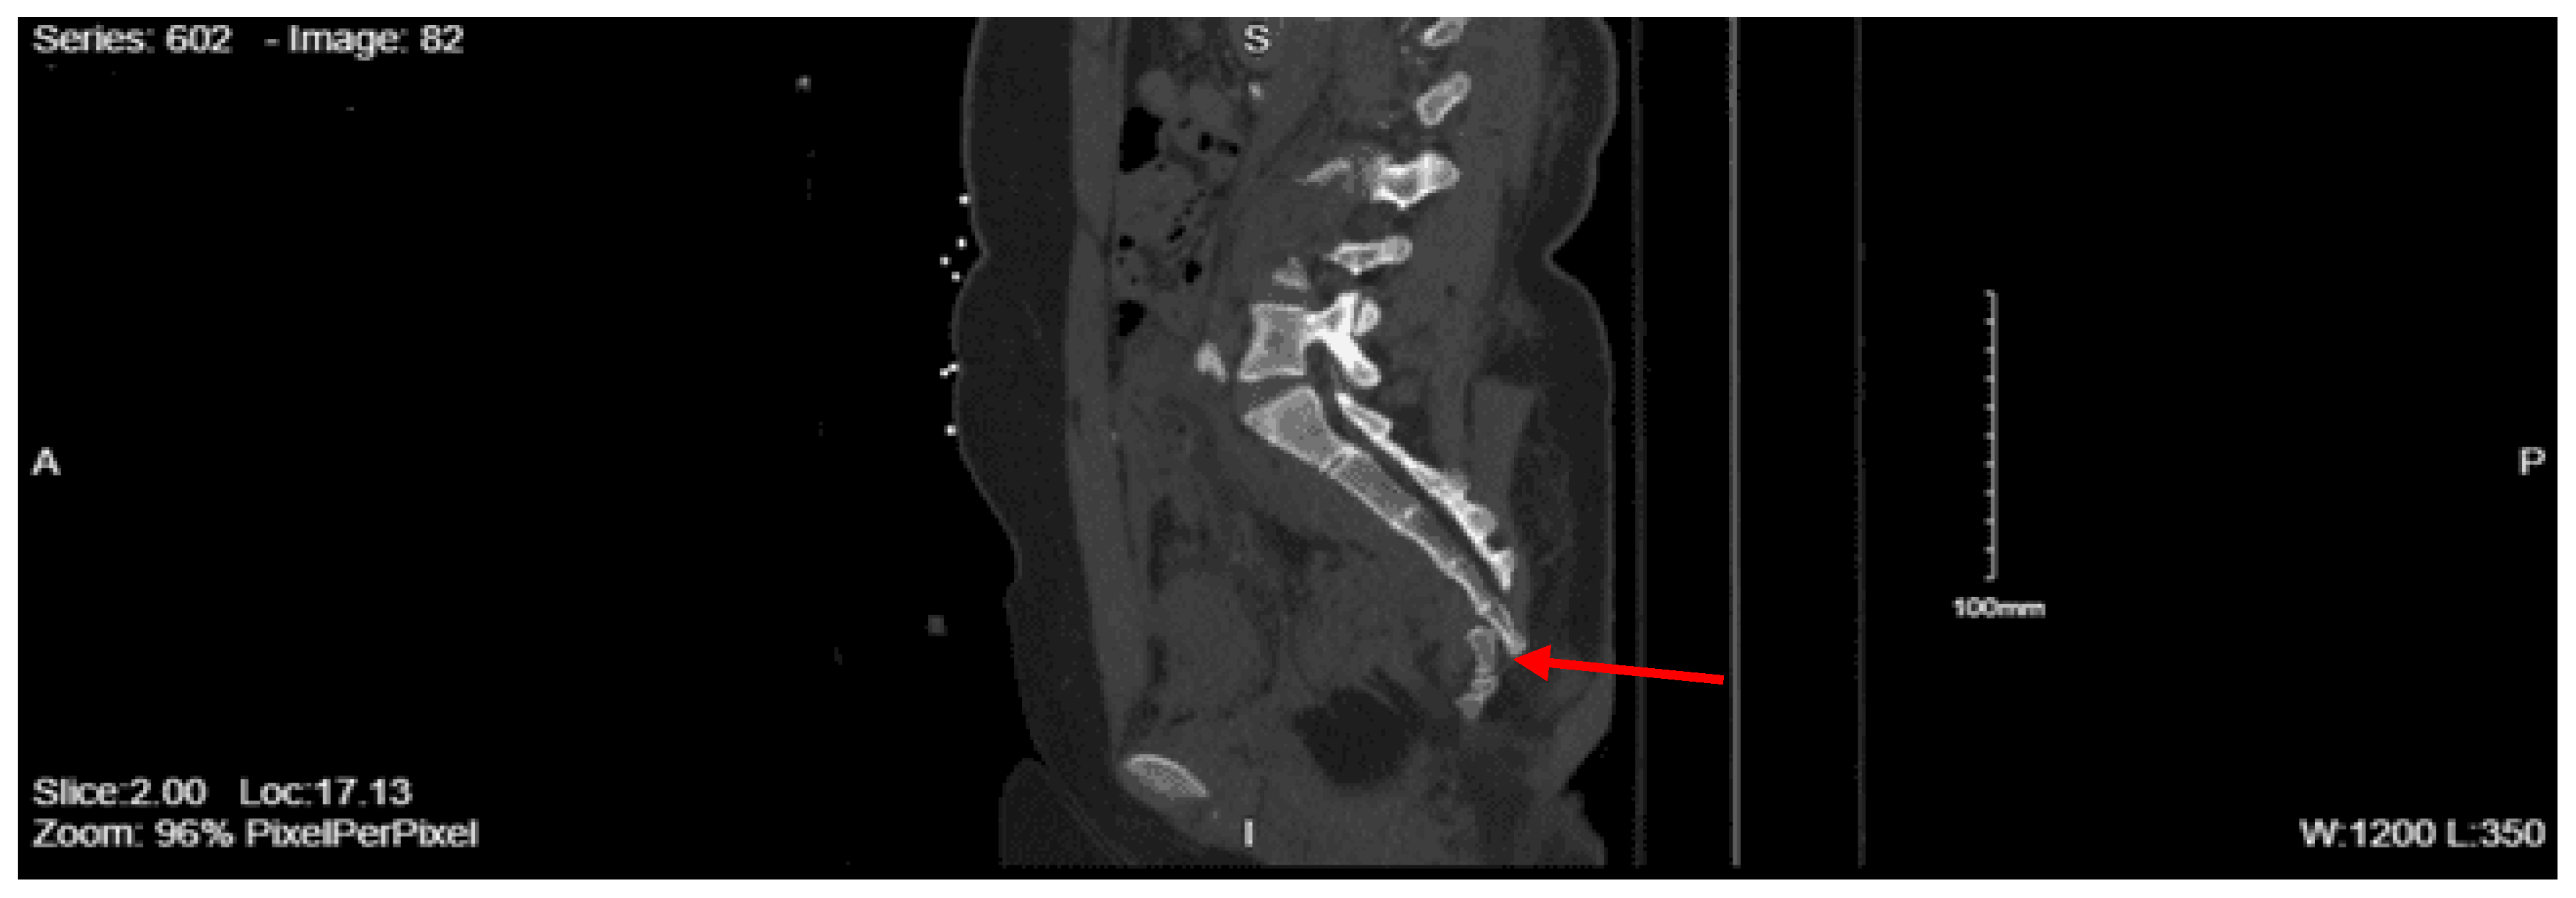

CT abdomen pelvis with contrast: There is retroperitoneal fluid surrounding the upper abdominal aorta without contrast blush. Linear flap within the upper abdominal aorta at the level of the celiac and SMA origins, concerning for traumatic injury. Lower thoracic findings include multiple posterolateral right rib fractures. Grade II hepatic injury. Periportal edema. Acute right L1 through L5 transverse process fractures. Acute right sacral ala fracture. Nondisplaced acute right inferior pubic ramus fracture. Nondisplaced acute fracture involving the lateral aspect of the right acetabulum.

Since the patient was found to have pneumothoraces and hemothorax, a right chest tube was inserted by the ED staff and connected to suction. Given the finding of suspected aortic injury from the CT abdomen pelvis with contrast, a CT angiography of the abdomen pelvis was performed, which showed no evidence of vascular abnormality. Pre-contrast imaging demonstrated a heterogeneous enhancement with persistent spotty nephrogram involving areas of the right kidney, which raised a concern for a renal contusion. The patient was admitted to the STICU for continued management of his traumatic injuries. Neurosurgery was consulted for the lumbar spine fractures and the sacral ala fracture. They recommended no acute surgical interventions and advocated for optimal pain control. Orthopedic surgery was consulted for the right sacral ala fracture and the lateral right acetabulum fracture, and recommended no orthopedic intervention at the time and no weight-bearing activity status. Psychiatry was consulted, given his history of psychiatric disease, and they recommended a two-to-one level of observation for unpredictable behavior, holding his standing home medications, and gave recommendations for agitation management.